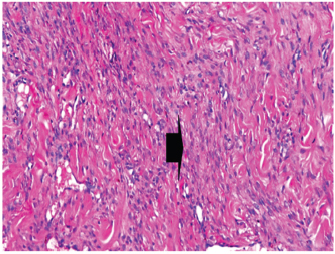

At 7 days post wounding; the inflammatory reaction was moderate and characterized by polymorphonuclear cells and macrophages infiltration with the presence of small scab covering the wound surface. Early evidence of epithelization was detected and represented by the proliferation of epidermal epithelium under the scab. There was marked thickening and hyperplastic proliferation of epidermal epithelium at the free wound edge (Fig. 6). The dermal tissue underlying the wound area showed few polymorphonuclear cells infiltration and more abundant mononuclear cells. Fibroplasia and angiogenesis were detected in the dermis and more extensive in deeper areas of the dermis which characterized by fibroblast and angioblast proliferation forming immature young granulation tissue (Fig. 7). At 14 days post wounding, the wound area was covered by a complete layer of epidermal epithelium indicating a good epithelization rate of the wound. Proliferation of cutaneous appendages was detected. The newly formed epithelium was thick and showed partial keratinization and epithelial differentiated stratum containing polyhedral keratinocyte with the appearance of keratohyalin granules in their cytoplasm (Fig. 8). The dermal tissue showed deposition of parallel well organized and interconnected collagen bundles that arranged parallel to epidermis associated with enhanced angiogenesis represented by well-developed blood capillaries (Fig. 9). At 21 days post wounding, remodeling of the formed epithelium with relatively small scar formation and mild restoration of skin appendages. Keratinized and differentiated stratum comprising the covering epithelium and the newly formed skin appendages from the basal epidermal epithelium were detected (Fig. 10). The dermal tissue revealed well-formed organized tissue consisted of parallel compact and interconnected bundles of collagen with scant angiogenesis (Fig. 11). At 28 days post wounding, well-formed scar tissue covering highly cellular organized tissue was detected (Fig. 12). The dermal tissue revealed well-arranged compact collagen bundles containing scarce blood vessels (Fig. 13).

Fig. 10. Skin of a goat from electroacupuncture group at 21 days post wounding showing keratinized (arrow head) and differentiated stratum comprising the covering epithelium (*) and the newly formed skin appendages from the basal epidermal epithelium (HE ×200).

Fig. 11. Skin of a goat from electroacupuncture group at 21 days post wounding showing well-formed organized tissue consisted of parallel compact and interconnected bundles of collagen with scant angiogenesis (arrow head) (HE ×200).